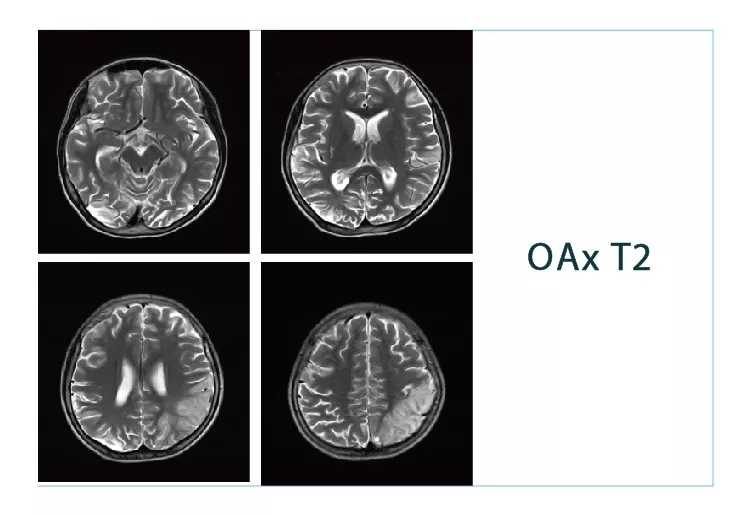

【朗润影像档案】20180817磁共振影像病例结果讨论